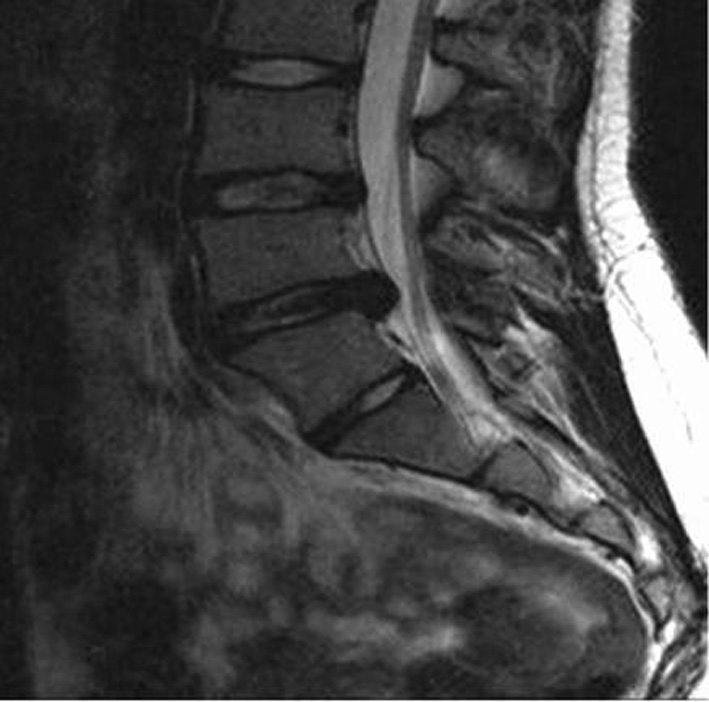

Six mois plus tard, le tableau persiste et une aggravation est perceptible depuis quatre mois. Une IRM est réalisée (clichés ci-dessous ; coupe axiale en L5-S1).

Quelle interprétation faites-vous de l’IRM ? Quel traitement proposez-vous ?